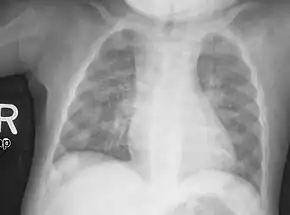

- Radiography typically show widening of the zones of provisional calcification of the metaphyses secondary to unmineralized osteoid. Cupping, fraying, and splaying of metaphyses typically appears with growth and continued weight bearing.[36] These changes are seen predominantly at sites of rapid growth, including the proximal humerus, distal radius, distal femur and both the proximal and the distal tibia. Therefore, a skeletal survey for rickets can be accomplished with anteroposterior radiographs of the knees, wrists, and ankles.[36]